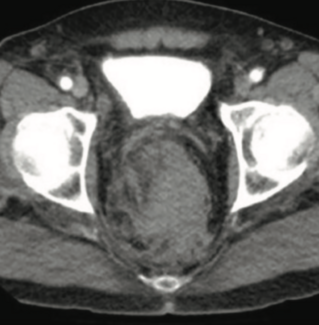

A 49-year-old man presented with chest pain. The patient had diabetes mellitus, hypertension, and had undergone coronary artery bypass graft surgery the year prior.